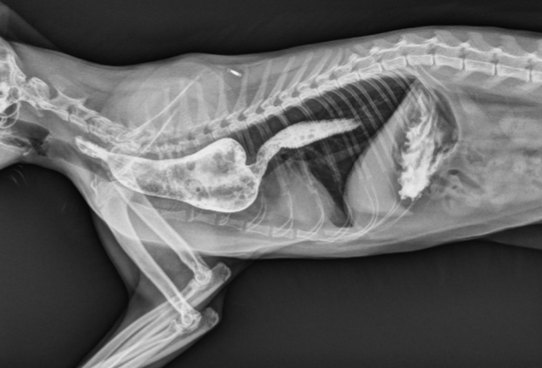

how is megaesophagus diagnosed?

-cervical and thoracic radiographs +/- oral contrast

-fluoroscopic swallow study

-thoracic radiographs: caudodorsal, gas-filled intrathoracic soft-tissue opacity

-contrast videofluoroscopy swallow study (normal does not rule out a hiatal hernia)